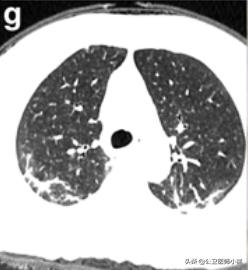

肺实变吸收后“融化的糖”样改变

肺部好转

如果患者得到有效的治疗,或者患者症状较轻免疫力成功抵御了病毒,炎症将进一步吸收程度开始降低。

开始恢复的肺